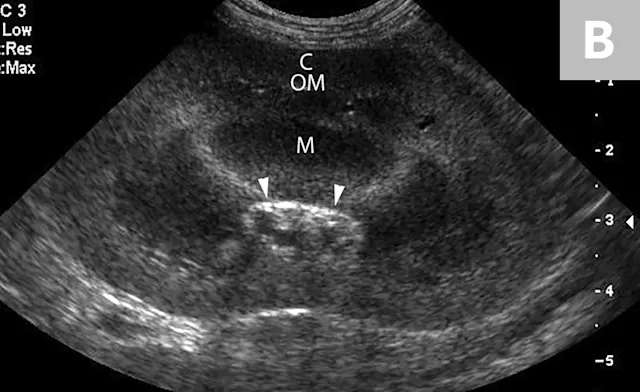

FIGURE 7A

Lateral abdominal radiograph of a cat with multiple, small, oval mineral opacities superimposed over the ventral aspect of the retroperitoneal space (arrows). These mineral opacities are arranged linearly extending from the caudal aspect of the kidneys to the level of the urinary bladder.